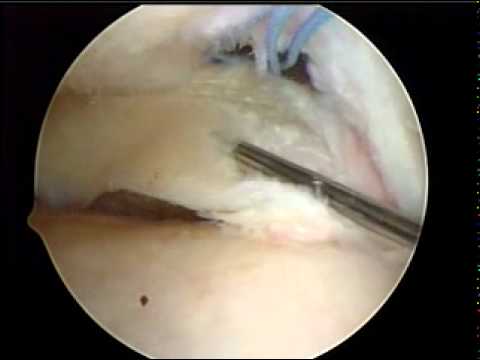

Suture méniscale d'une fissure longitudinale de la corne postérieure :

comment soigner menisque

Chirurgie méniscale :